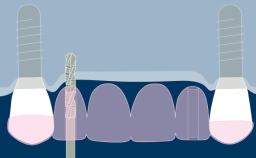

- discuss the importance of denture base fit and extension for denture retention and support

- describe the aspects of denture design that aid in restoring the patient’s overall physiognomy and oral function